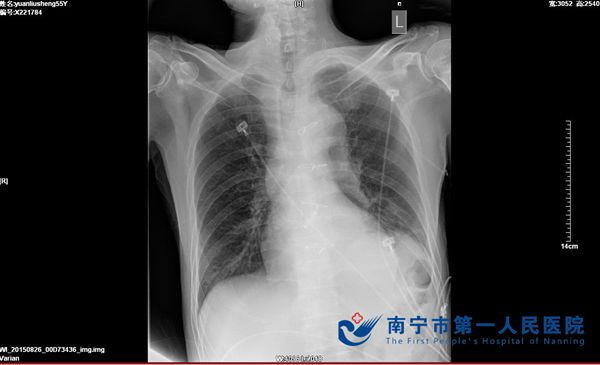

“终于得好好呼吸一口气了”这是今年9月25日袁伯伯拔除气管插管后说的第一句来,其实作为全科医务工作者都知道,对于他来说呼吸好一口气实在太不容易了。原来袁伯3月前行主动脉瓣置换术后因出现肺部感染等较多并发症需长期呼吸机辅助呼吸,曾行气管切开术,待他心脏病情稳定后,却反复出现气喘表现而多次加重心脏功能,需多次入住重症监护室,直至最后一次插管发现困难及经纤支镜检查,才真正证实气管狭窄所致,此翻经历对于袁伯伯来说苦于难言...